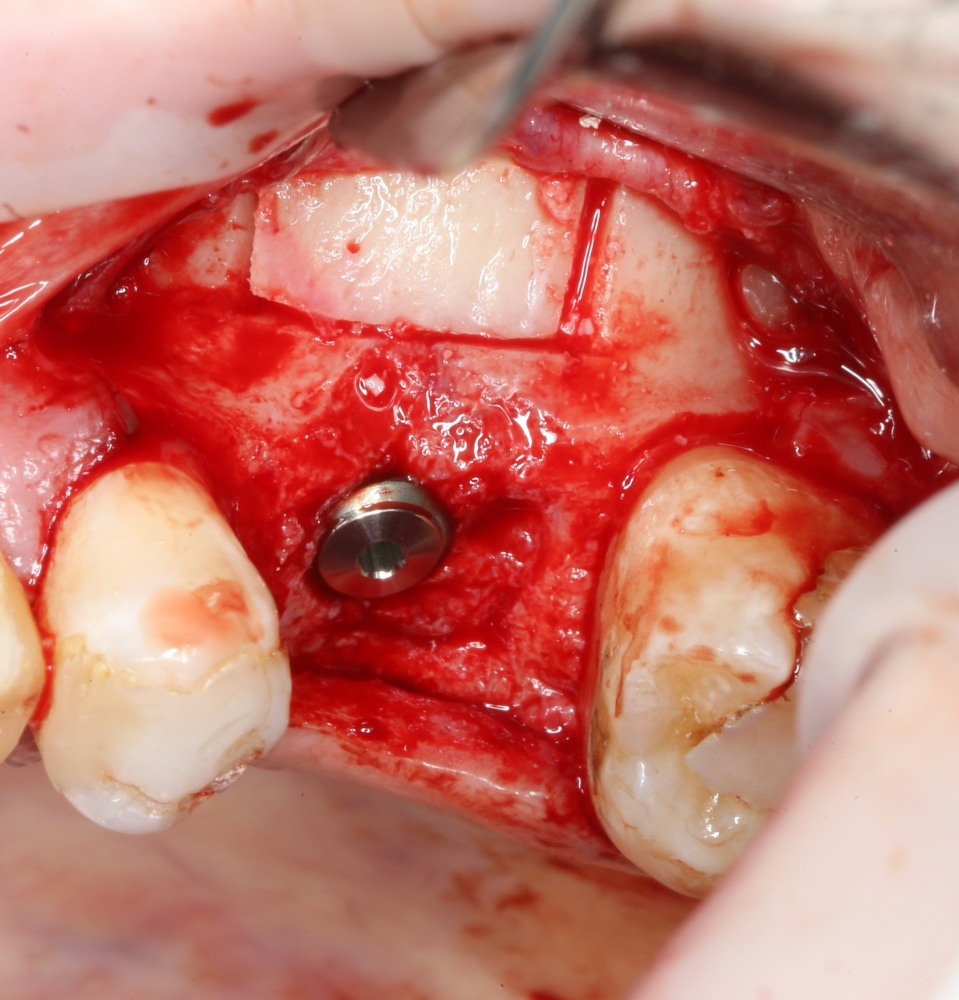

В общем, мы с вами не придурки слесари-столяры, периимплантита не хотим, поэтому кортикальные фрезы не игнорируем:

Кортикальная фреза погружается строго до отметки (см выше). В нашем клиническом случае (с синуслифтингом) это особенно важно, чтобы имплантат не улетел в субантральное пространство. Таким образом получаем лунку, полностью конгруэнтную будущему имплантату. Это очень-очень важно:

Пришло время вернуться к синуслифтингу и заполнить сформированное ранее субантральное пространство графтом (Geistlich Bio-Oss Pen):

запечатываем заполненное субантральное пространство:

Приступаем к установке имплантата.